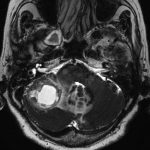

530

'24年5月

50代

小脳血管芽腫

頭蓋内腫瘍摘出術

No.’24_32 手術前1

No.’24_32 手術前2